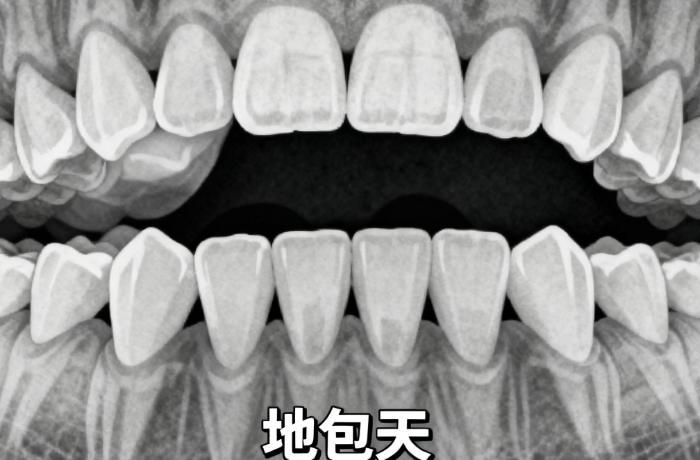

2、矫正难度:简单的牙齿排列不齐,矫正时间短,价格相对低,如轻微拥挤可能3000-10000元;复杂的咬合问题或较重畸形,矫正时间长且方案复杂,价格可达20000-50000元。